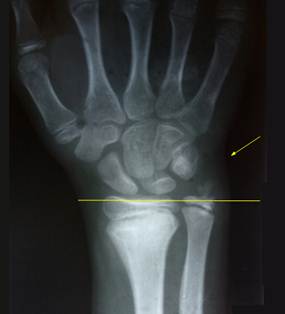

Снимок

описываемого больного слева, справа приведен снимок предплечья здорового ребенка

такого же возраста. Обратите внимание на соотношение уровней концов локтевой и

лучевой костей. На снимке слева заметен контур руки и её деформация (отмечена

стрелкой).